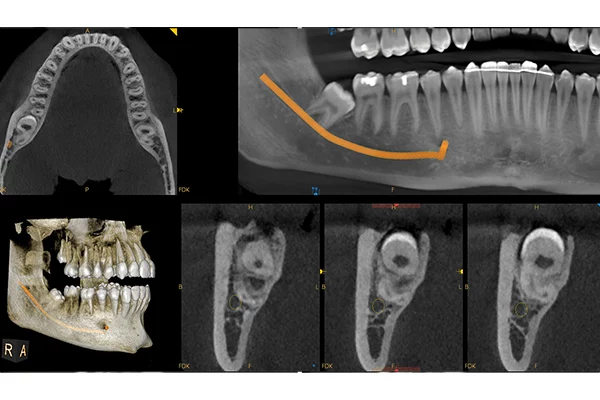

CBCT + OPG

• Automatické vytvoření OPG pohledu z CBCT skenu

• Automatické vytvoření projekce Ortho z CBCT skenu (AP, PA, LAT,)

• MAR patentované potlačení artefaktů s živým náhledem efektu filtru pomocí nezávislého algoritmu 3D (zcela unikátní)